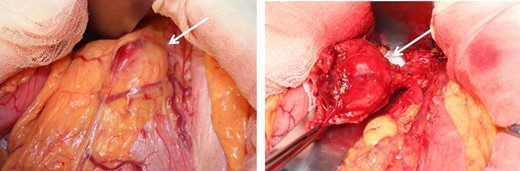

At laparotomy, a well-encapsulated tumor was found in the lesser omentum. It was slightly adhered to the stomach wall but could be removed without difficulty (Fig. 3). There were no obvious lesions of peritoneal dissemination or lymph node metastasis. Therefore, only enucleation of the tumor was performed. The excised tumor, which was 35 × 30 × 25 mm3 in size, had a white cut surface without necrosis or hemorrhage (Fig. 4). Histologically, the tumor was composed of spindle-shaped cells with an interlacing bundle pattern exhibiting microcystic changes and moderate cellularity (Fig. 5a). No mitotic figures were observed. Immunohistochemistry revealed the tumor cells to be positive for c-KIT (CD117) (Fig. 5b), myeloid stem cell antigen (CD34) (Fig. 5c) and α-smooth muscle antigen (α-SMA) (Fig. 5d) and negative for S-100 protein (Fig. 5e). Based on Fletcher’s classification, the tumor was classified as a low-risk GIST originating in the lesser omentum. The patient had an uneventful postoperative course. Presently, the patient is alive, without recurrence, and is doing well 3 years after the surgery without imatinib treatment.

Operative findings. At laparotomy, a well-encapsulated tumor was found in the lesser omentum. It was slightly adhered to the stomach wall but was removed without difficulty.

Macroscopic findings of the resected specimens. The excised tumor, which was 35 × 30 × 25 mm3 in size, had a white cut surface without necrosis or hemorrhage.